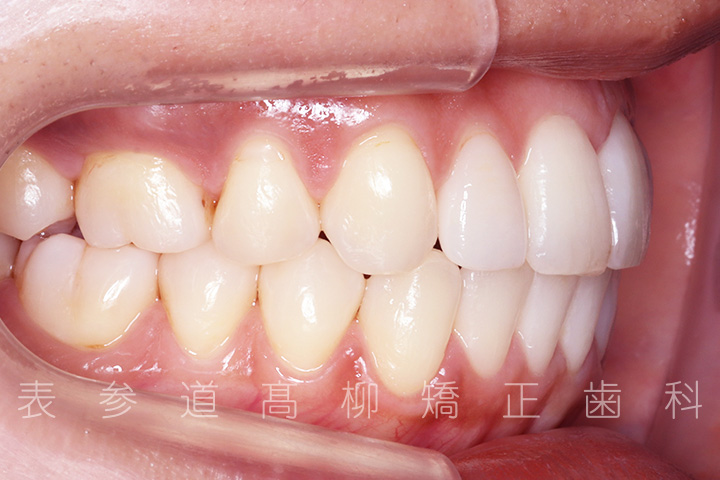

上の前歯が出ているのと前歯が小さいことをお悩みの患者様の症例をご紹介いたします。

・上顎前突(前歯の前方傾斜)

・2⏊2矮小歯(先天的に形態が小さい歯)

・上下前歯部叢生(凸凹歯並び)

・上顎左側第一小臼歯、右側第二小臼歯を抜歯

・前歯部の叢生(ガタガタ感)を改善

・歯科矯正用アンカースクリューを併用し、前歯部を後方へ移動する

・上下歯列の緊密な咬合関係の確立に顎間ゴムを併用(装着時間20時間以上/日)

・アライナーによる嚙み合わせの微調整

・矯正治療終了後 加部歯科医院(https://kabe-dent.net) にて2⏊2補綴処置を行った